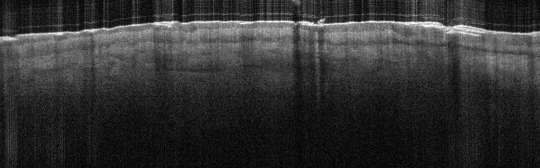

VA9: Left Forearm, Adjacent Normal